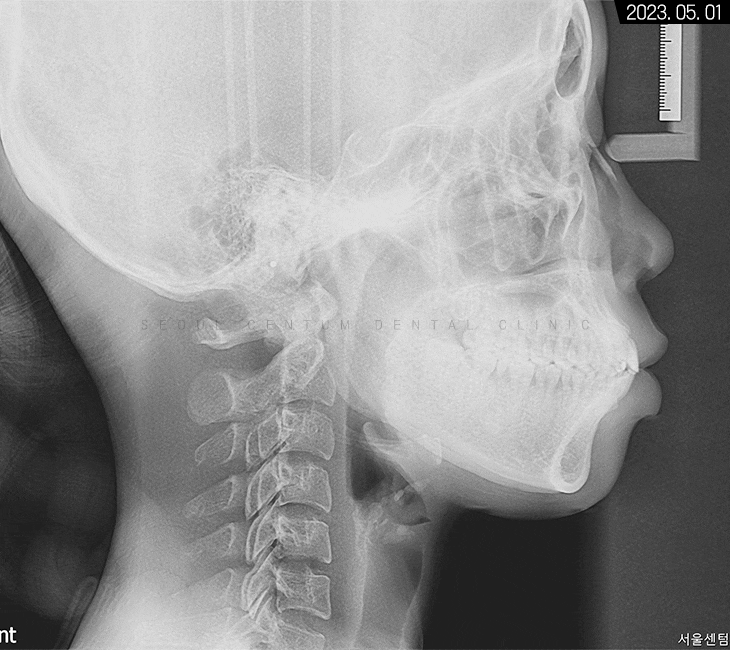

세팔로 측면 사진을 보면

확실히 수평피개 상태가 눈에 띄고

코끝부터 턱 끝까지 심미선을 그었을 때

입술이 과하게 넘어간 것을 볼 수 있었는데요.

입이 튀어나와서

아래턱이 들어간 양상도 보이지만

치아 전돌을 해소하면

아래턱이 자연스럽게 전상방으로 올라와서

구조적으로 정상 범주에 돌아오게 됩니다.

치조골 상태는 양호해서

치근 이동에 무리가 없을 것으로 예상됐고요.

측면에서는 브라켓이 구치부부터

전치부까지 고르게 붙어있는 것을 볼 수 있고

아직까지 도톰한 입술과 뭉툭한 턱 또한 보입니다.

에스테틱 라인도 아직은 만들어지지 않아

경과를 지켜보기로 했습니다.